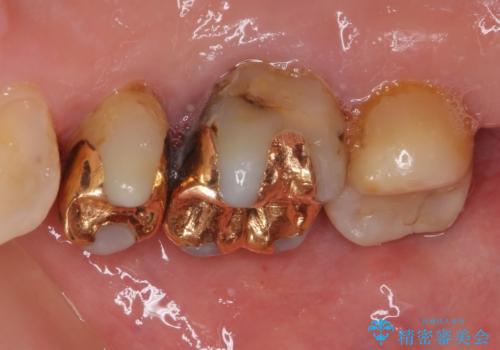

- 奥歯の裏側がしみるとのことで来院された患者様です。

矯正治療による歯肉退縮がおき、歯根にまで虫歯が波及していました。

虫歯が大きかったため、フルジルコニアクラウンにて補綴することとしました。